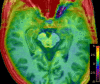

Methods: In this cross-sectional study, 20 patients with aMCI and 20 age- and gender-matched healthy controls (HCs) underwent MEGA Point Resolved Spectroscopy (MEGA-PRESS) and APTw MR imaging at 3 T. GABA+, Glx, and APTw signals were measured in the right hippocampus. The GABA+ levels, Glx levels, Glx/GABA+ ratios, and APTw values were compared between the HCs and aMCI groups using the Mann-Whitney U test. Binary logistic regression and receiver operating characteristic (ROC) curve analyses were used to evaluate MEGA-PRESS and APTw parameters' diagnostic performance.